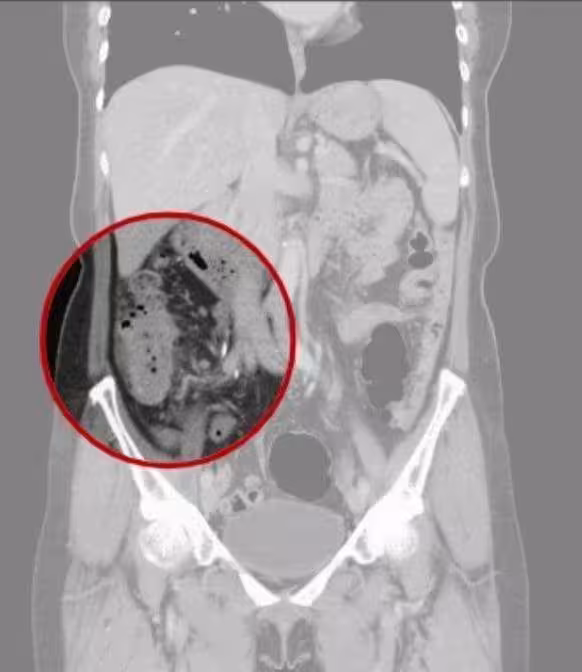

半小時就1人大腸癌!台中女第4期冒3症狀,醫嘆:已轉移肝

無大腸癌相關病史 台中女確診已癌末據了解,已婚的吳女無大腸癌相關家族史與病史,但4月時她突然受到腹痛、血便及噁心困擾,就醫檢查時驚見自己升結腸有8*5公分腫瘤,同時胃部也有5*3公分的高惡性風險胃腸道基質瘤,